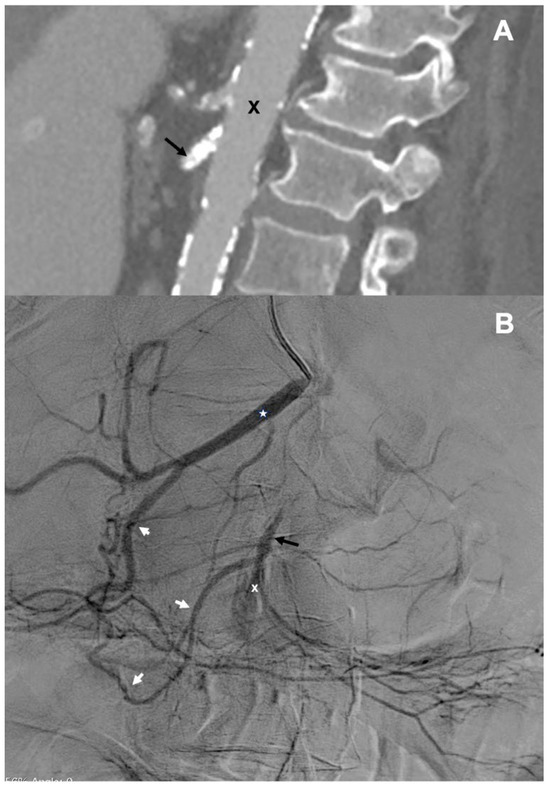

First, we introduced a 5F vertebral diagnostic catheter to the distal part of the CHA, then the coaxial Progreat microcatheter (Terumo, Tokyo, Japan), which was navigated through the GDA and the pancreaticoduodenal arteries (PDA) to the SMA distally from the occluding plaque (Figure 2A). Thereafter, the occlusion that was highly calcified was crossed with 0.014″ and then 0.018″ guidewires. From the right brachial access, we introduced another 6F introducer sheath, which was placed at the level of the SMA. Guidewire, which has been previously navigated to the abdominal aorta across the lesion through the celiac trunk, the CHA, the GDA, the PDA, and the proximal SMA, was caught with a loop (Figure 2B). Then, through the 6F introducer sheath, in an antegrade direction, we introduced 2.5/20 mm and 4.0/20 mm Trek coronary dilatation catheters (Abbott Vascular, Abbott Park, IL, USA), and with these balloons, we predilated the plaque under the pressure of 6–18 atm.

Figure 2.

(A)—Microcatheter (white arrow) advanced to the superior mesenteric artery (black arrow) through the gastroduodenal and pancreaticoduodenal arteries; (B)—Guidewire (white arrows) navigated in a retrograde manner across the lesion to the aorta caught to the introducer sheath (black arrow).